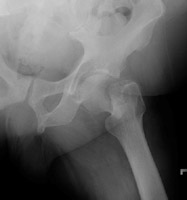

- Click on the image for a larger versionDAP radiograph of the left hip. Two years later, the patient presents with hip pain and a femoral neck fracture (basicervical).